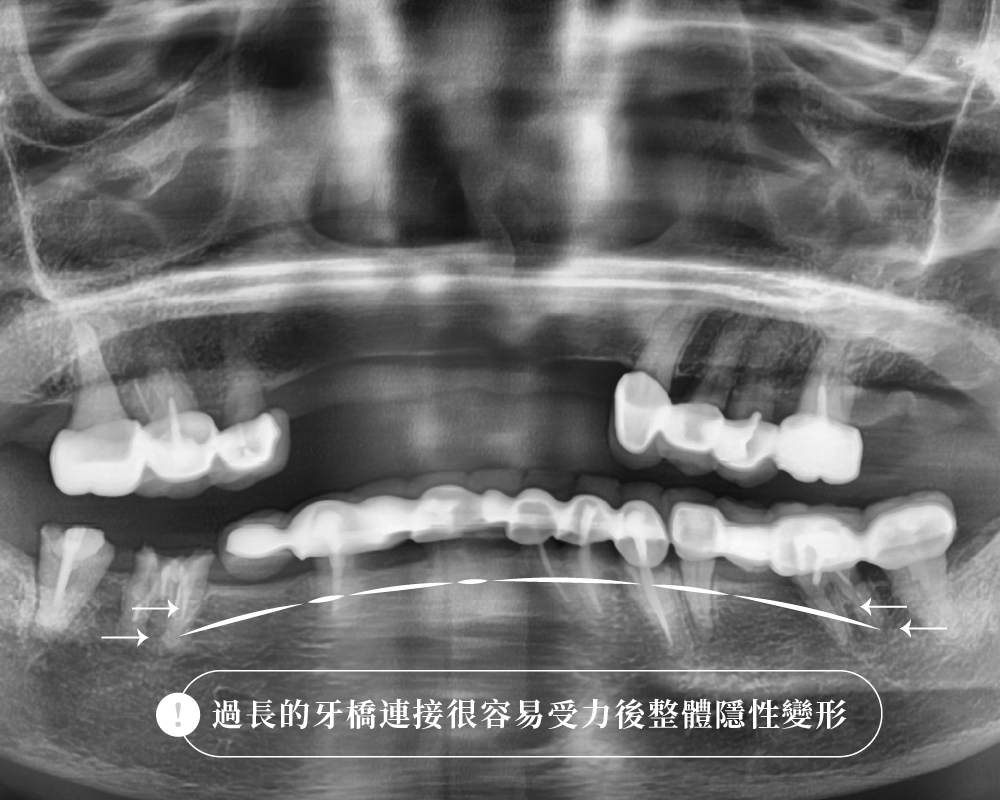

- 橋體越長,形變與彎曲風險會明顯增加;

長牙橋越容易彎、越容易累積應力,這不是單純多一點點而已,而是會被放大。

在固定贋復學裡,這個原理是經典觀念;Shillingburg 的《Fundamentals of Fixed Prosthodontics》明確整理了這個力學原則:橋體撓曲與跨度長度呈立方關係,與咬合齦向厚度呈反比的立方關係。

也就是說,在其他條件近似時,跨度加長,形變會明顯放大,而不是線性增加。這個經典說法在後續贋復文獻中也持續被引用,常追溯到 Stuteville 1934 年的早期報告。

越長的牙橋,受力、彎折、支柱牙負擔、邊緣密合、長期清潔與二次蛀牙風險,都會跟著改變。